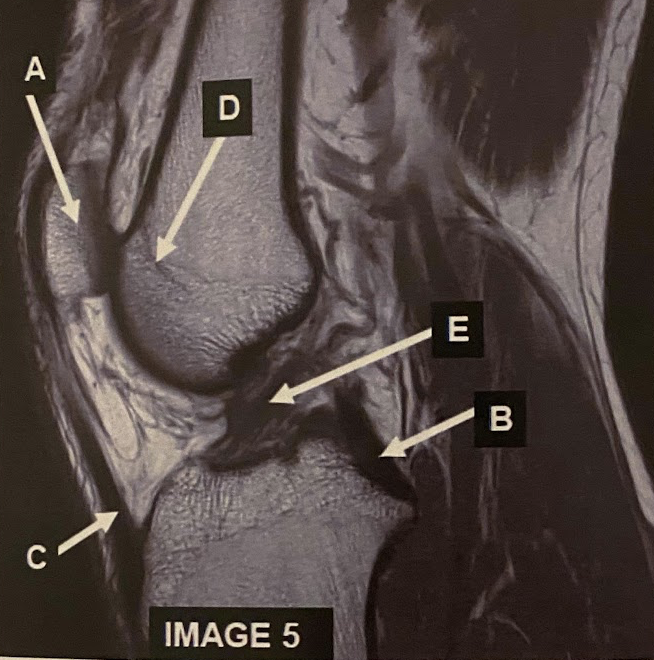

20

What anatomy does letter A demonstrate?

Patella

21

What anatomy does letter B demonstrate?

PCL

22

What anatomy does letter C demonstrate?

Patellar Tendon

23

What anatomy does letter D demonstrate?

Femoral Condyle

24

What anatomy does letter E demonstrate?

ACL

Which plane best demonstrates the anterior cruciate ligament? A) coronal B) Axial C) Sagittal oblique

C) sagittal oblique